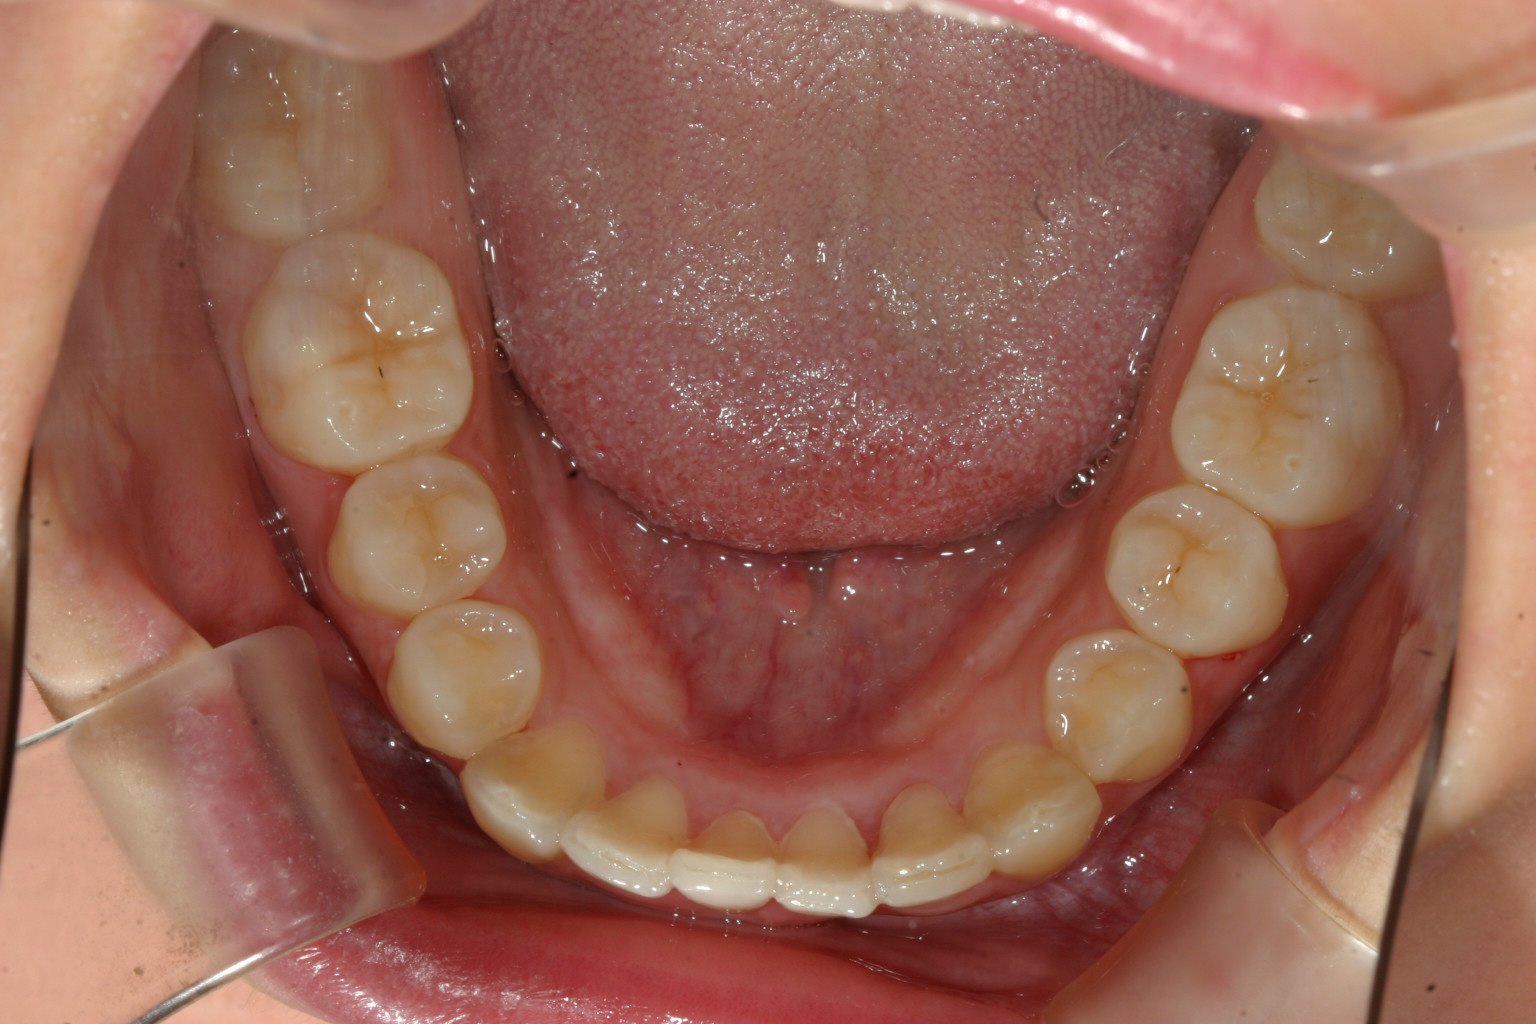

上を先に出して下の前歯も綺麗に並べました。

綺麗なオーバーバイトに改善しました。

前歯に自家製のバイトアップジグを院長自ら製作しアップダウンエラスティックで臼歯の咬合を挙げてます。

こちらの症例はかなりのオーバーバイトの為、自家製バイトアップジグにて咬合を挙げた症例です。